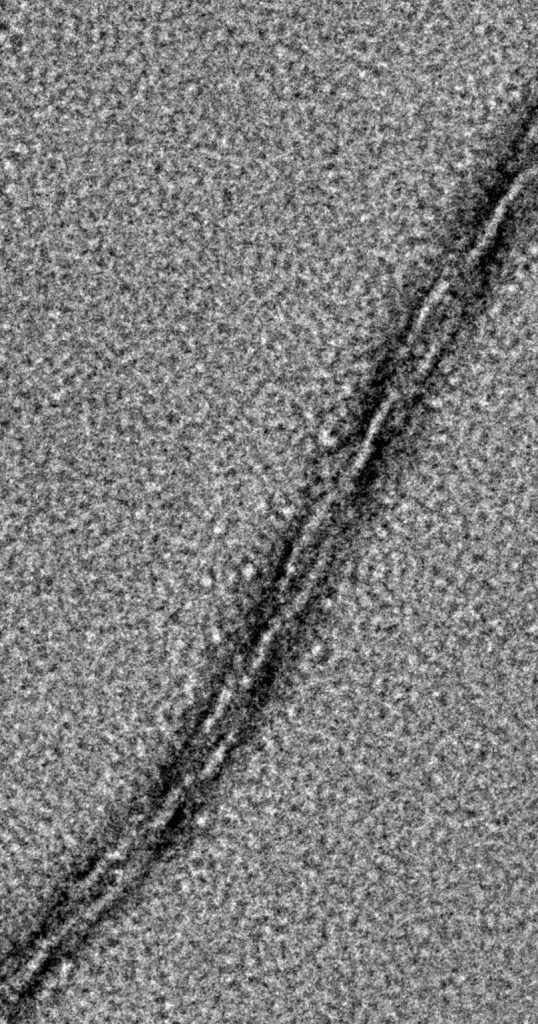

Aggregation of proteins and peptides into toxic amyloid structures is a critical biological event that leads to the onset of several pathological conditions including Alzheimer’s disease, Huntington’s disease, Parkinson’s disease, etc. This decade has observed an upsurge in the prevalence of more than 50 amyloidogenic diseases. We will be working to gain a mechanistic understanding of the protein aggregation process, including its structural insights, and apply this fundamental knowledge to study the molecular events in protein aggregation and its pathology in neurodegenerative diseases.